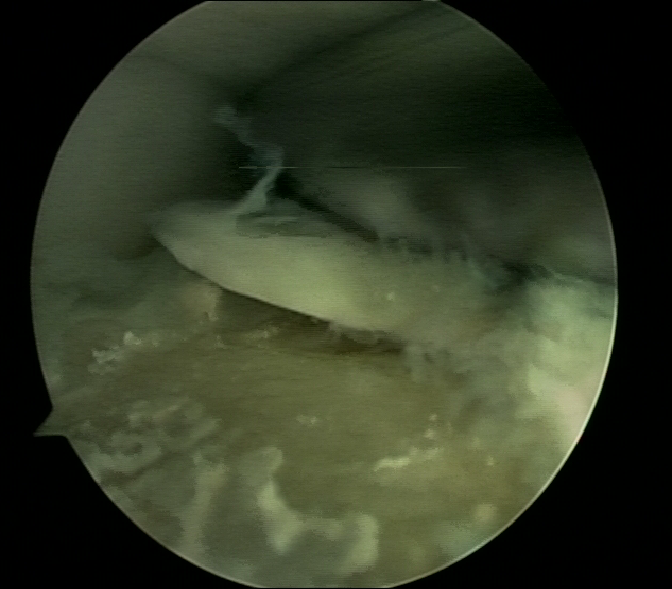

软骨退变

游离体形成

关节清理术后

清除的骨赘及游离体

软骨剥脱

软组织撞击